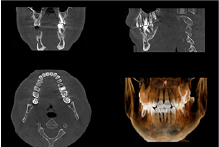

サージカルガイドは、インプラント手術の正確性を飛躍的に高めるために開発された、カスタムメイドのマウスピース状の器具です。

事前のCT検査やシミュレーションで導き出された「インプラント埋入の最適な位置、角度、深さ」を、このガイドが手術中に正確にアシストします。

これにより、血管や神経などの重要な組織を傷つけるリスクを最小限に抑え、シミュレーション通りの安全で低侵襲な手術を実現します。術後のトラブル防止にも大きく貢献し、患者様により安心できるインプラント治療を提供します。

2精密検査と治療計画のご提案

安全かつ確実な治療の土台を築くため、歯科用CT、レントゲン、口腔内写真撮影など、各種精密検査を実施します。高性能な設備を用いてお口や顎の骨の状態、そして全身の健康状態まで正確に把握し、インプラント治療の適性を判断いたします。

検査結果に基づき、診断内容と治療計画を詳細にご提案いたします。必要なインプラントの本数、治療にかかる費用、期間など、すべてを丁寧かつ分かりやすくご説明します。当院では「インフォームドコンセント(説明と同意)」を徹底しておりますので、ご不明点や不安な点は遠慮なくご質問ください。治療計画にご理解・ご納得いただき、十分にご検討いただいた上で治療をスタートします。